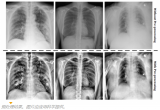

使用肺部X射线诊断COVID-19

2020年7月22日- 塞维利亚大学计算机工程学院(ETSII)计算机架构和技术系的研究人员正在研究一种使用患者肺部X射线图像帮助诊断COVID-19的系统。 2020-07-24 产业应用